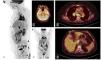

Pruebas complementariasEn el estudio analítico destacó un IGRA (ensayo de liberación de interferón gamma) negativo y unos niveles elevados de la enzima convertidora de la angiotensina 116U/L (normal 13-63,9). La PET-TAC confirmó la existencia de conglomerados adenopáticos hipercaptantes en el mediastino, los huecos supraclaviculares y el retroperitoneo (fig. 3A-C), junto a 3 nódulos pulmonares (fig. 3D). Además, se observaron nódulos subcutáneos hipercaptantes en las localizaciones anteriormente descritas y en las regiones mamaria e interglútea (fig. 3B-D), con un SUVmáx promedio de 6.